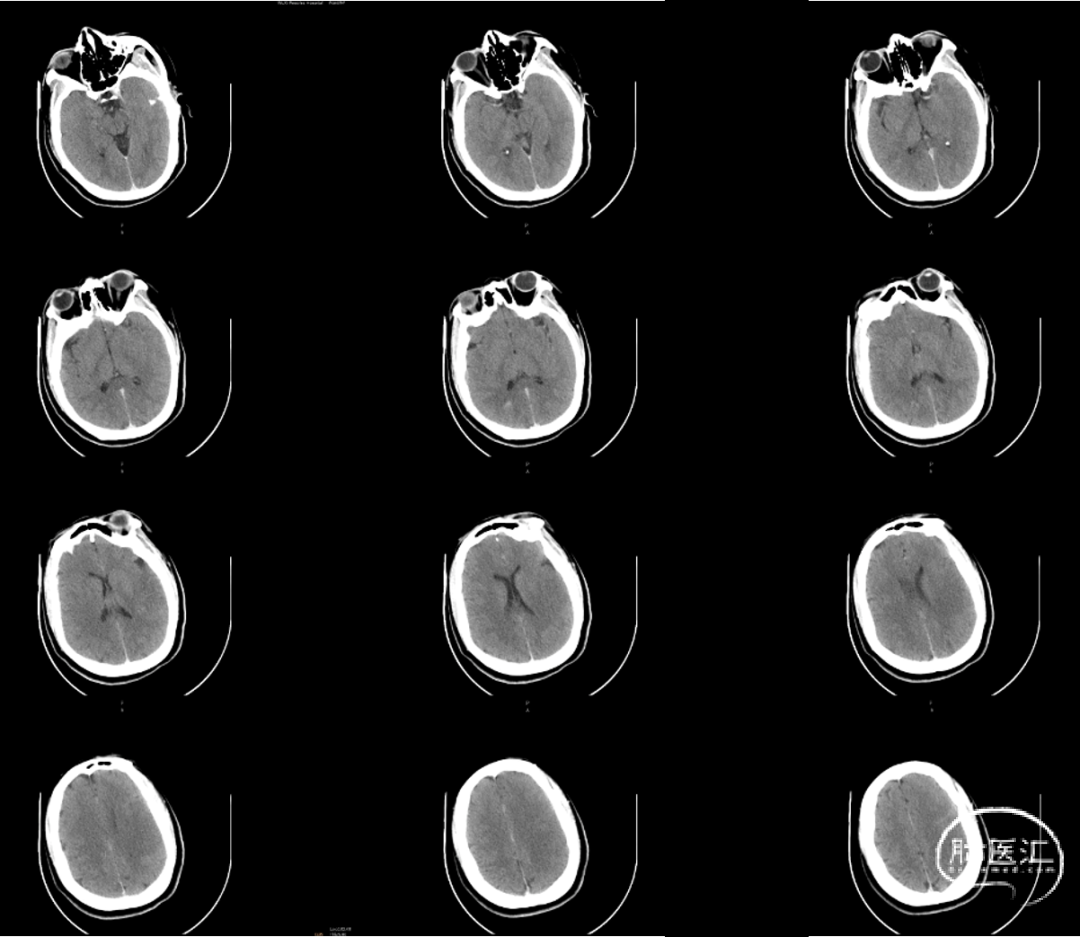

术前平扫CT:未见明显异常。

术后即刻CT:

术后造影及CT提示:左侧颈内动脉开通,血流灌注达mTICI 2c级,造影剂无外渗,远端分支血管部分闭塞。